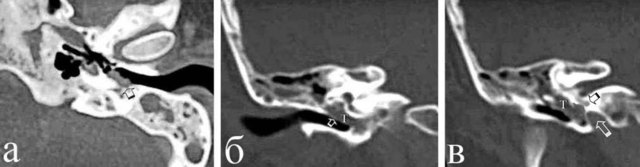

Невринома уха

Невринома уха 116 фотографий